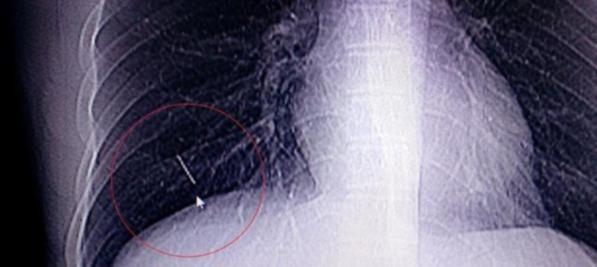

Denizli'de, bir hastanın göğsündeki iğne ameliyatla çıkarıldı.

Hastanın çekilen röntgeninde göğüs boşluğunda yaklaşık 2 santimetrelik iğne tespit edildi.

Genel Cerrahi Uzmanı Doç. Dr. Namık Özkan ve ekibi tarafından ameliyata alınan Erkan Değirmenci'nin göğüs duvarındaki iğnenin kesin yeri skopi cihazıyla ile belirlenerek çıkarıldı.